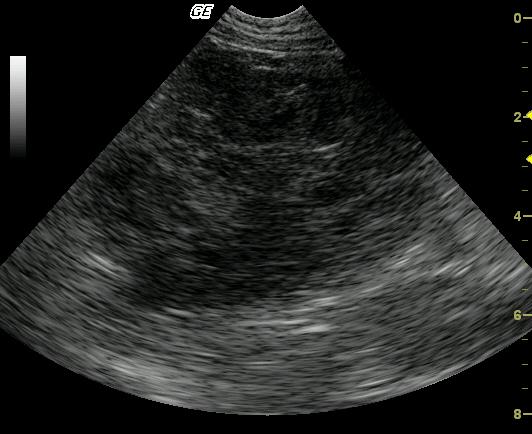

Long-axis view of the left lateral liver lobe reveals a large (5-cm), lobulated, complex, mixed echogenic, nodular mass arising from the left caudal liver. The mass is causing caudal displacement of the stomach, which was not in the view. The remaining left liver demonstrates a mildly echogenic parenchyma with evidence of portal venous congestion.